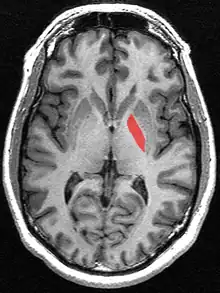

Globus pallidus

Globus pallidus (in red) shown within the brain

The globus pallidus (GP), also known as paleostriatum or dorsal pallidum,[1] is a subcortical structure of the brain. It consists of two adjacent segments, one external, known in rodents simply as the globus pallidus, and one internal, known in rodents as the entopeduncular nucleus. It is part of the telencephalon, but retains close functional ties with the subthalamus in the diencephalon – both of which are part of the extrapyramidal motor system.[2] The globus pallidus is a major component of the basal ganglia, with principal inputs from the striatum, and principal direct outputs to the thalamus and the substantia nigra. The latter is made up of similar neuronal elements, has similar afferents from the striatum, similar projections to the thalamus, and has a similar synaptology. Neither receives direct cortical afferents, and both receive substantial additional inputs from the intralaminar thalamus.